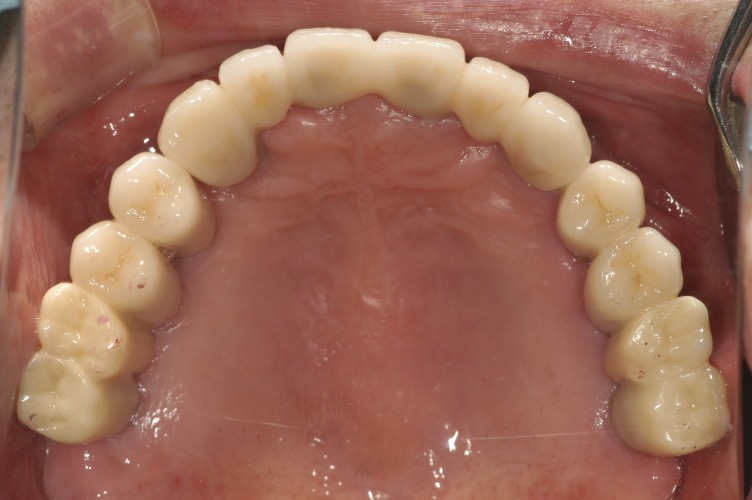

뼈가 좋은부위에서 임플란트시술은 어렵지 않으나, 뼈가 부족해서 뼈이식 혹은 윗니 어금니의 경우 상악동거상술이 필요하거나, 혹은 앞니의 경우 다른 경우보다 보다 섬세한 계획과 시술이 필요합니다.

임플란트는 약 20년전에는 수입임플란트를 많이 하였으나, 최근엔 국내임플란트를 거의 모든 경우에 식립을 하고 덴티스 혹은 오스템임플란트를 사용하고 있으며, 뼈 상태가 약하면 하이드록시 아파타이트가 코팅된 덴티스헵타이트를 사용하고 있습니다.

임플란트 비용은 120만원입니다. 뼈이식비용은 발치를 했는 부위라면 30만원, 상악동저거상술이 필요한경우 50-100만원 비용이 듭니다.

어금니의 경우 예를 들어 3개가 없다면 2개를 심고 한개를 앞뒤 걸어서 할수 있는데 거는 치아는 50만원비용이 듭니다.